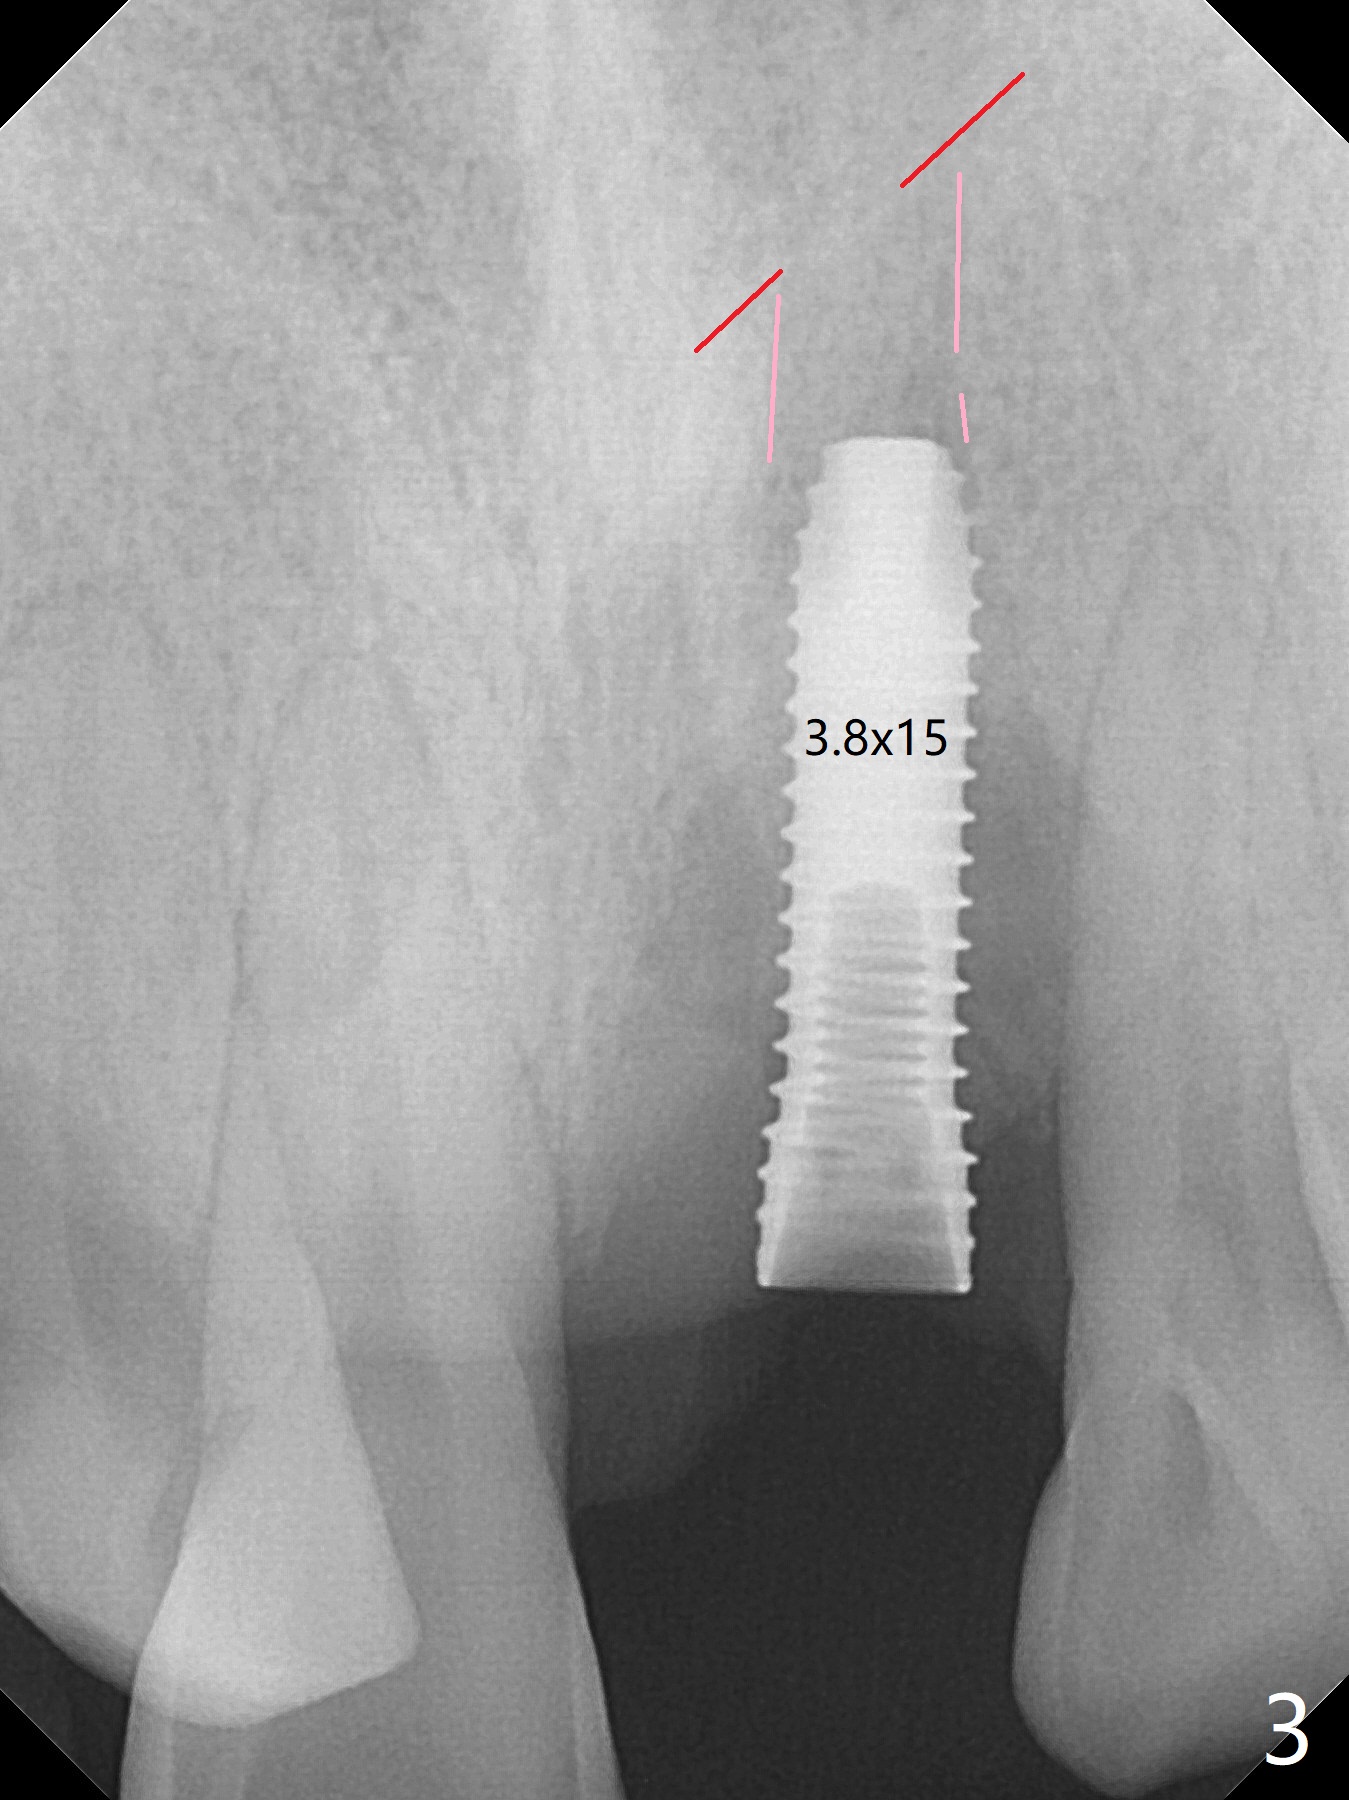

Immediately preop PA confirms loss of the buccal plate at #9 (Fig.1 *). In contrast the palatal crest is ~ 4 mm subgingival (WNL) after extraction. When initial osteotomy reaches 18 mm, there is moderate hemorrhage, probably due to close to the nasal floor (Fig.2 red dashed line). Following sequential osteotomy, a 3.8x15 mm dummy implant is placed partially (Fig.3 (pink: apical osteotomy)). After placement of an implant with the same dimension as the dummy's (Fig.4), PRF is laid against the inner surface of the buccal defect and allograft (Fig.5 *) is packed mainly in the buccal gap before and after insertion of a 4.5x5(4) mm abutment. The patient is satisfied with the immediate provisional (Fig.6: 1 week postop). The buccal margin of the provisional is shortened with exposure of bone graft to facilitate gingival downgrowth (Fig.6: 1 month postop). The buccal plate seems to collapse nearly 2 months postop (Fig.8 *), probably due to loss of the bone graft. The abutment is exposed buccally (Fig.9). The margin of the abutment is reprep and the provisional is relined so that the margin of the provisional is palatal to the buccal gingival margin. In 2-3 weeks, a temporary abutment will be used to bulk the buccal gingiva. The gingiva seems to have downgrown; the buccal plate collapse appears normal nearly 3 months postop (Fig.10). The patient is more concerned about cross bite at #7. A temporary abutment is not used. The bone graft remains in place 3.5 and 4.5 months postop (Fig.11,12 *). Between 3 and 4 months postop, the mesial surface of the abutment has been trimmed (Fig.12 >). Since the mesial surface of the tooth #10 will be reduced (white curved line) to correct the upper dental midline, an angled abutment (red line) seems to be necessary to shift the provisional distal.